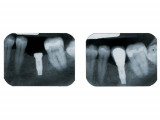

Un implant dentaire est une racine artificielle placée par le chirurgien-dentiste dans l'os alvéolaire de l'un des maxillaires en remplacement de la racine d'une dent extraite et servant de support à une prothèse.

Sa forme est généralement cylindrique ou légèrement conique, ressemblant à une vis, en titane ou en zircone, avec une connexion au niveau supérieur, à l'emplacement de la gencive, pour permettre la pose d'un élément prothétique par vissage ou scellement.

Son diamètre varie entre 3 et 5mm et sa longueur entre 8 et 15mm.